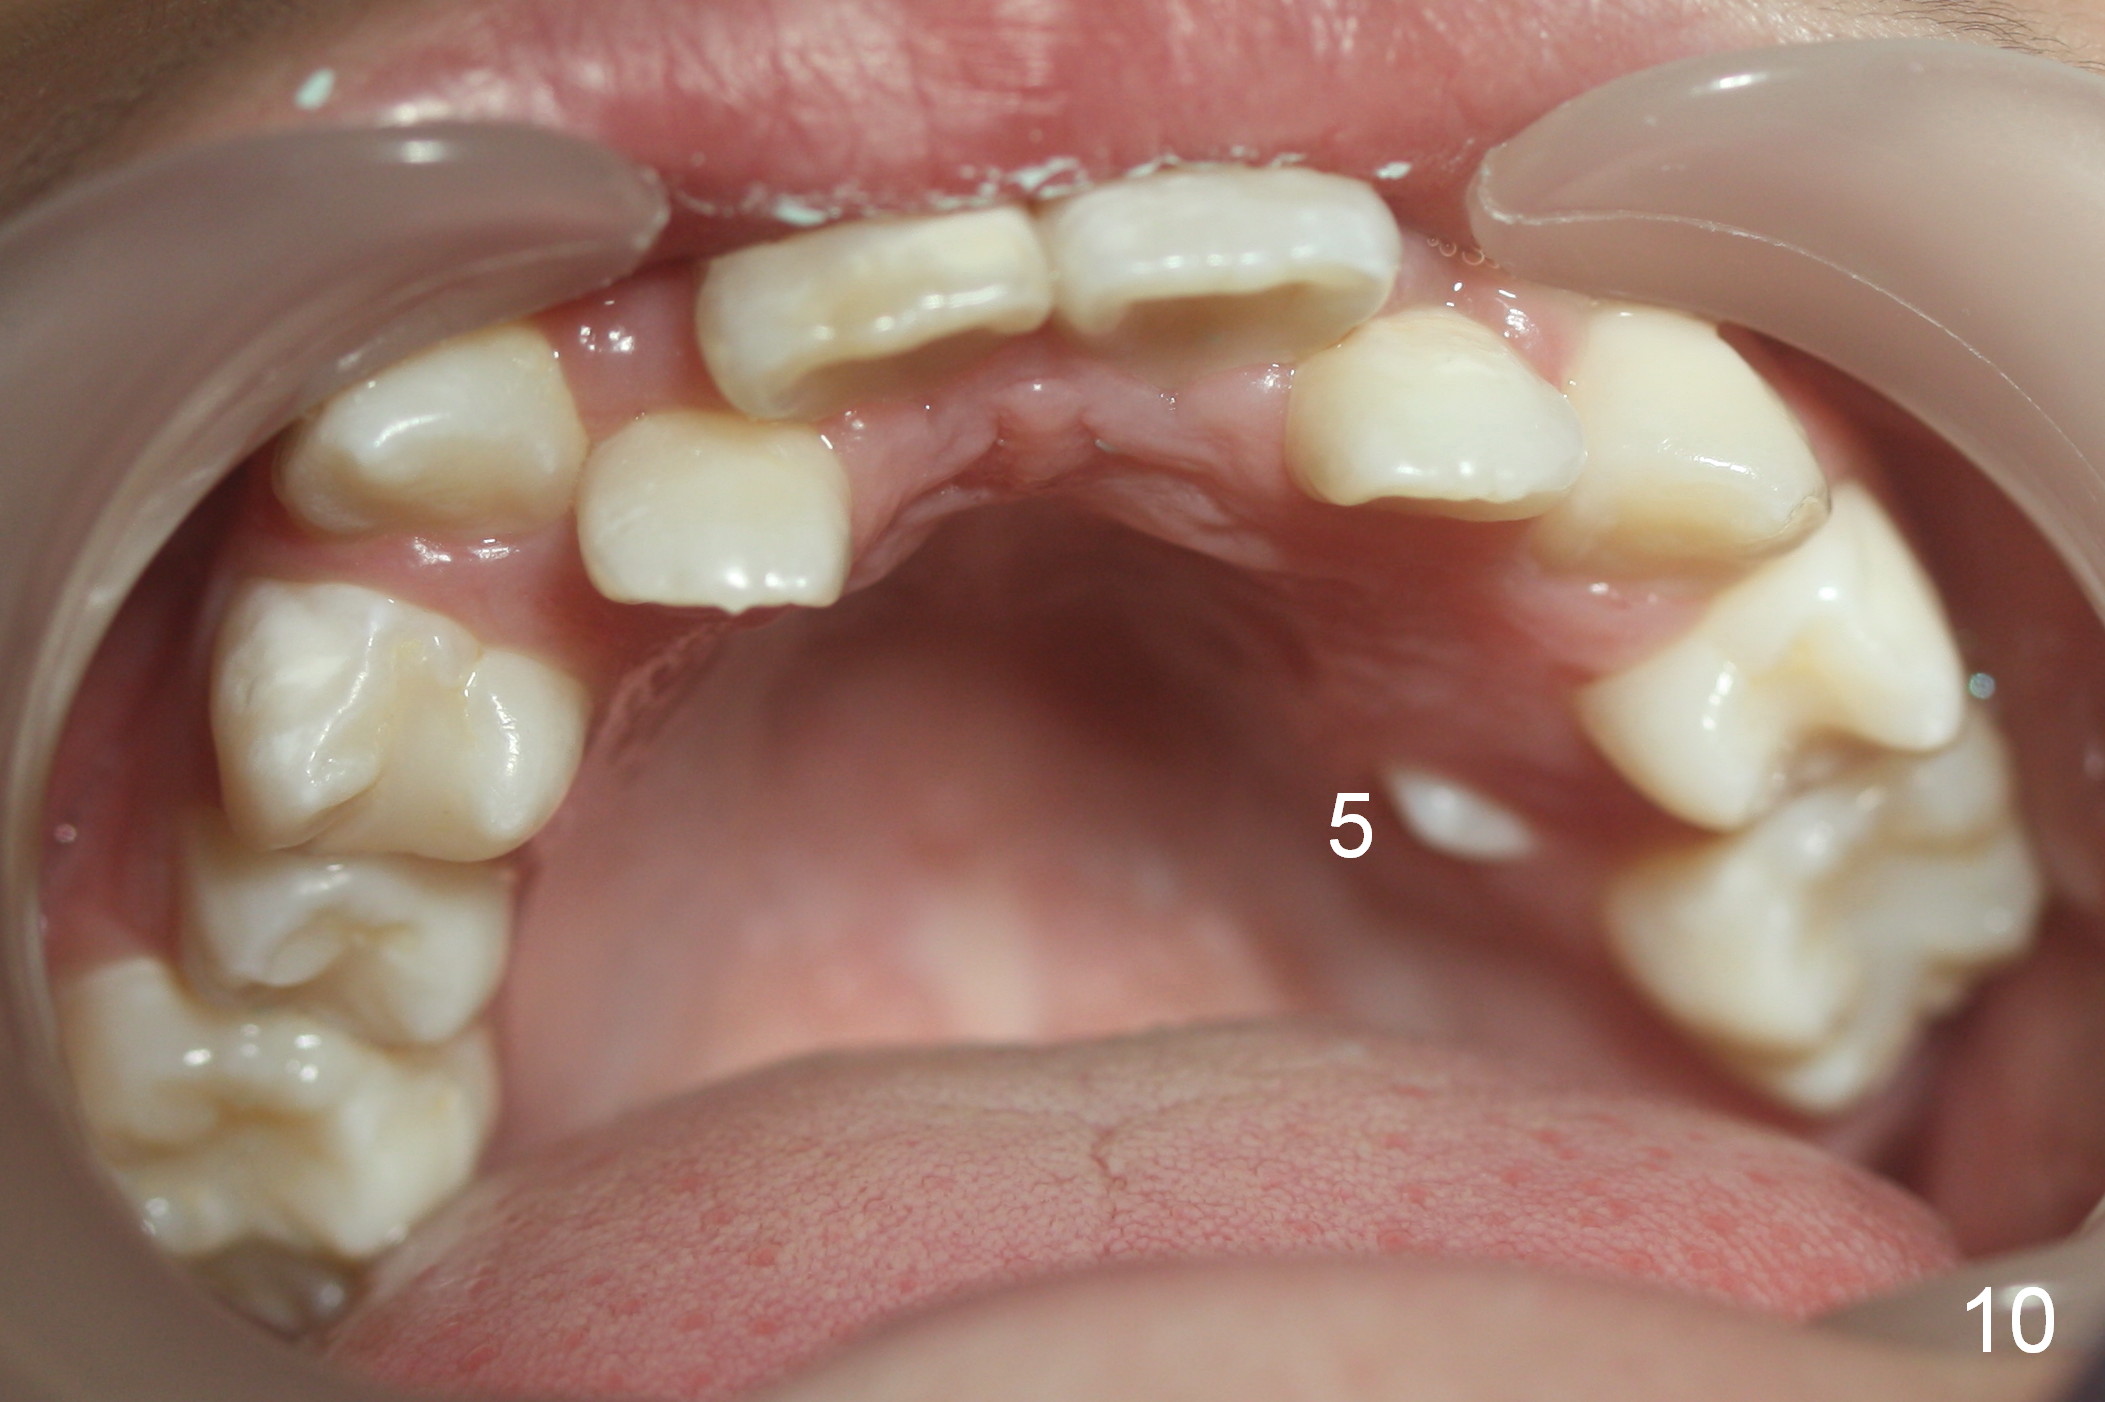

A 10-year-old girl with history of hyper-thyroidism has severe Class I malocclusion. She is ready for treatment. There is mild lip strain (suggesting anterior tooth protrusion, Fig.1,3). The facial and dental midlines coincide (Fig.2). Severe crowding is evident. Extraction orthodontics is indicated, either next to the most crowded areas (UR, LR4, Fig.6) or impacted ones (UL, LL5, Fig.10,11 (mirror view)).

When L3s is repositioned normally, try to mesialize the posterior teeth so that L7s have space to erupt (Fig.5).